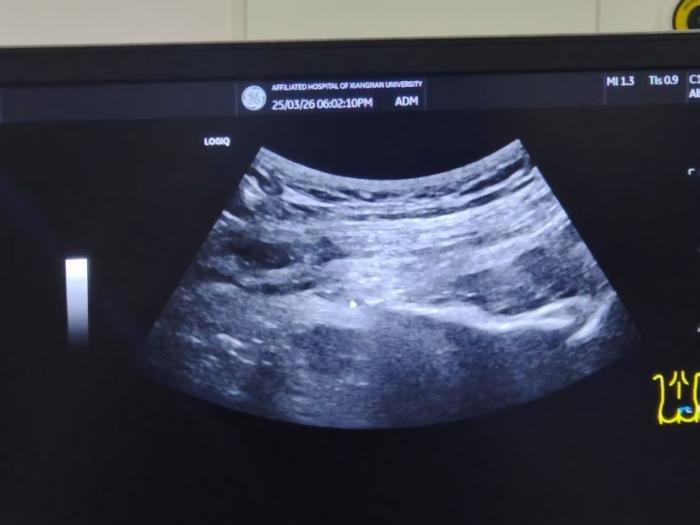

明确病因后,疼痛科迅速安排李奶奶在超声引导下行双侧阴部神经射频脉冲术。术后第一天,李奶奶就激动地拉着杨主任的手说道:“做完手术,我疼痛好多了,太感谢你们了!” 经过 4 天的术后观察,李奶奶的症状没有反复,最终,她和家属带着满意的笑容办理了出院手续。